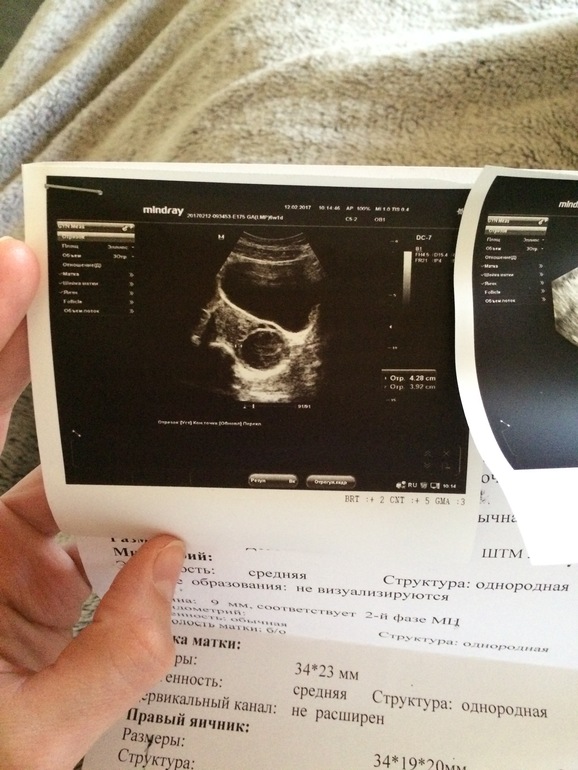

узи

8 день задержки узи 118 фотографий